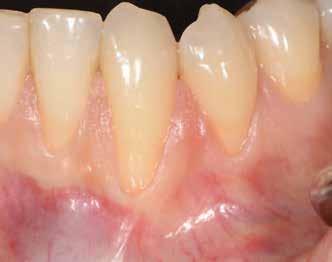

1. ábra: Műtét előtti fogászati panorámafelvétel, amelyen a hiányzó felső állcsont jobb első premolárisát és a szabad véggel rendelkező hidat láthatjuk. — 2. ábra: Az implantátum méreteinek megtervezése CBCT-vel. 3. ábra: Bukkális lágyrészdefektus. — 4. ábra: A biológiai szélesség értékelése a vertikális lágyszövetvastagság alapján. 5. ábra: Palatinális „tekercslebeny” – Palatal roll flap. — 6. ábra: Bredent medical copaSKY 4x10 implantátumbeültetés. 7. ábra: Szubkresztális implantátumbeültetés a várható biológiai szélességnek megfelelően.

8. ábra: Egyéni ínyformázó titánbázison, tulipán alakú emergenciaprofillal. — 9. a. ábra: A sebzárás okkluzális nézete.

(2. ábra). A lágyszövetek értékelése Seibert szerinti I. osztályú csontdefektust állapított meg (3. ábra), ezért a beavatkozáskor palatinális „tekercslebenyt” preparáltunk (palatal roll flap), és implantációt végeztünk, hogy kompenzálni tudjuk a bukkális lágyszövet-behúzódást. Megmértük a vertikális lágyszövetvastagságot, és úgy terveztük, hogy a szubkresztális implantátum beültetése összhangban legyen a biológiai szélesség kialakulásával a transzgingivális gyógyulási periódus alatt (4. ábra)

Az eljárást helyi érzéstelenítés mellett végeztük (4%-os articaine-hidroklorid 1:100 000 adrenalinnal). Papillakímélő, U alakú palatális bemetszést végeztünk, teljes vastagságú nyálkahártyalebeny preparálás történt, a lebenyt bukkálisan feltekertük (5. ábra). A lebeny bukkálisan feltekert részén de-epitelizációt végeztük el, amellyel kompenzálni tudtuk a bukkális lágyszöveti defektust. Szakaszos előfúrást végeztünk, és a bredent copaSKY 4x10 implantátumot 30 Ncm behajtási nyomatékkal helyeztük be (6. ábra). Az implantátumot 1 mm-re szubkresztálisan helyeztük be, hogy később szélesebb emergenciaprofilt tudjunk kialakítani (7. ábra). Az egyedi ínyformázó úgy készült, hogy kompozitot vittünk fel a titánbázisra, és így formáztuk a lágyszöveteket a transzgingivális gyógyulási fázis során (8. ábra). Az egyéni ínyformázó tulipán formájú, hogy kialakítsa a kívánt emergenciaprofilt. A lágyszövetet feszülésmentesen zártuk #6/0 nem felszívódó, monofil fonallal (Optilene, B. Braun Deutschland; 9. a–b. ábra). Posztoperatív röntgenfelvétel készült, ami alapján az implantátum a szomszédos fogakkal párhuzamos elhelyezést mutatott (10. ábra). Posztoperatív utasításokat adtunk a páciensnek a műtéti terület körüli szájhigiénia fenntartása érdekében. A beavatkozást követő egy héttel a varratokat eltávolítottuk, és a kezelt terület kielégítő gyógyulást mutatott (11. ábra). A 4 hónap utáni késleltetett terhelést a páciens kívánsága szerint terveztük.